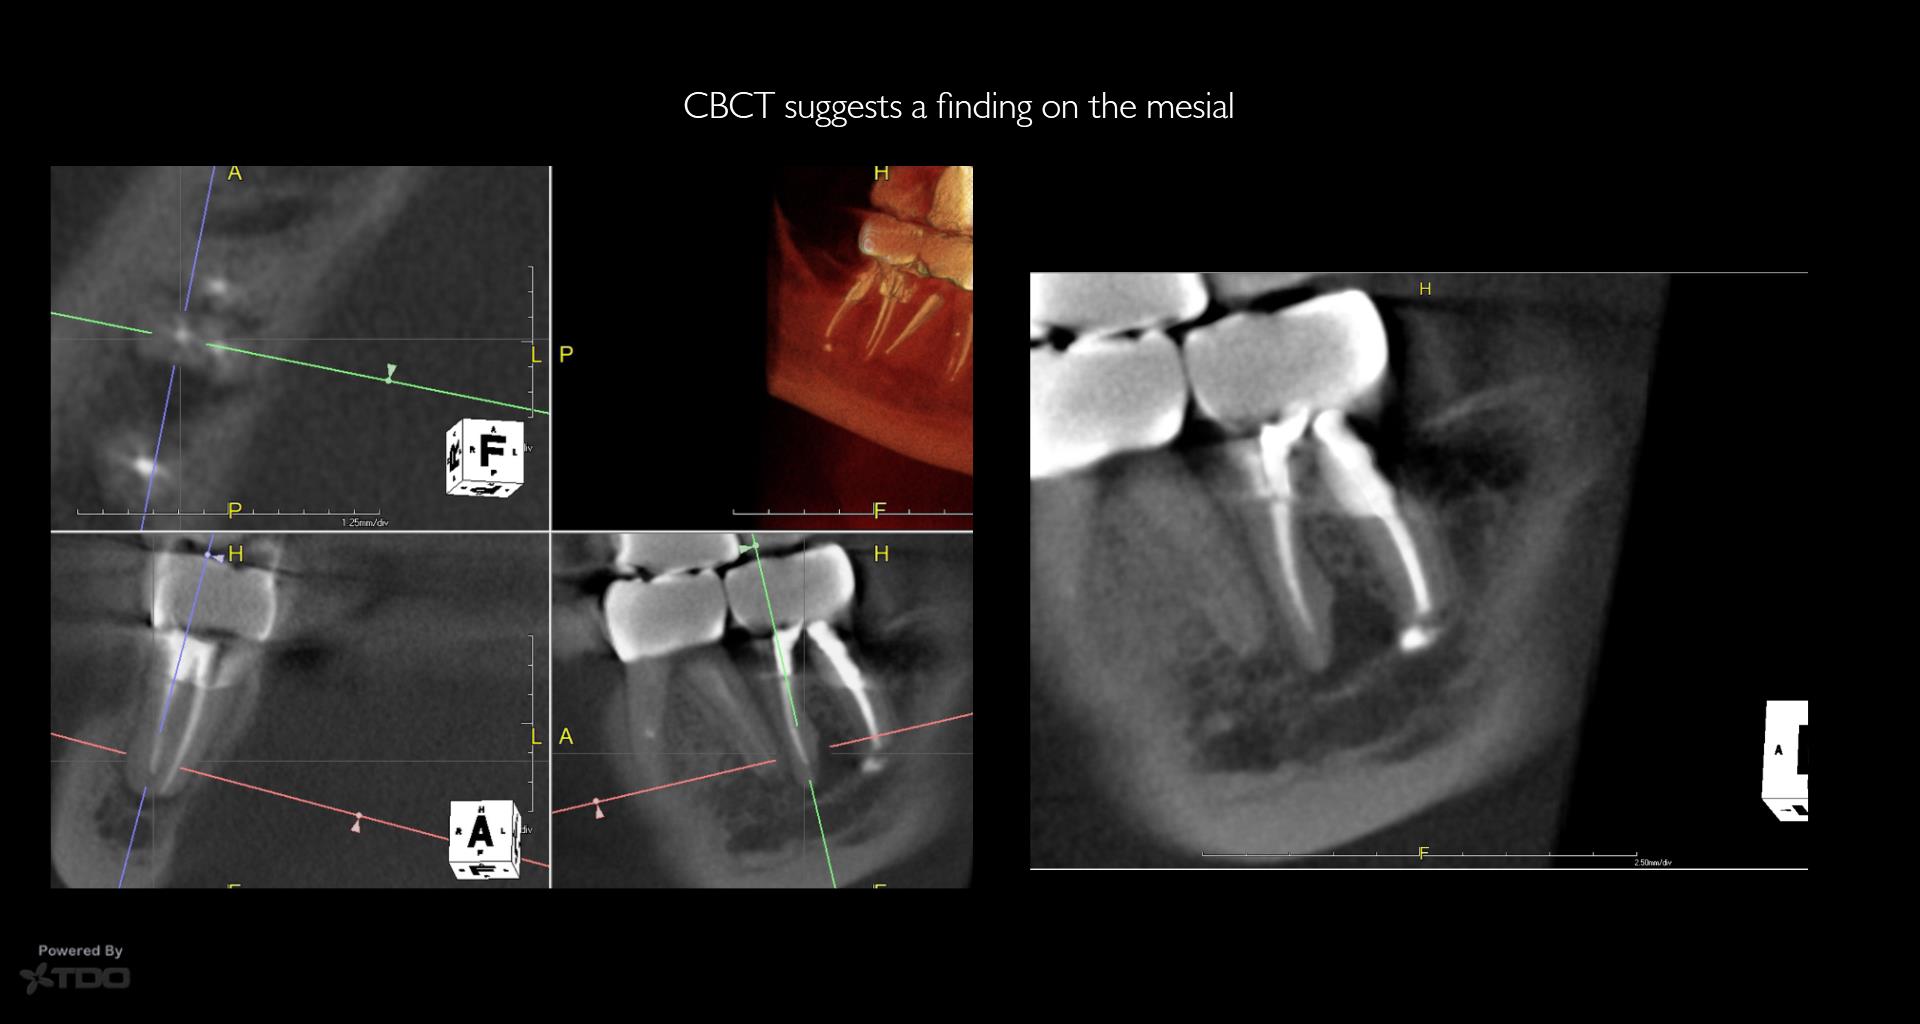

Very compliant patient—always made his recalls. Tooth has been asymptomatic for 15 years…and the periapical area had cleared—-now tender to biting and patient has an ache….No evidence of any occlusal issues. Will start the retreatment…again. Ugh….. gbc